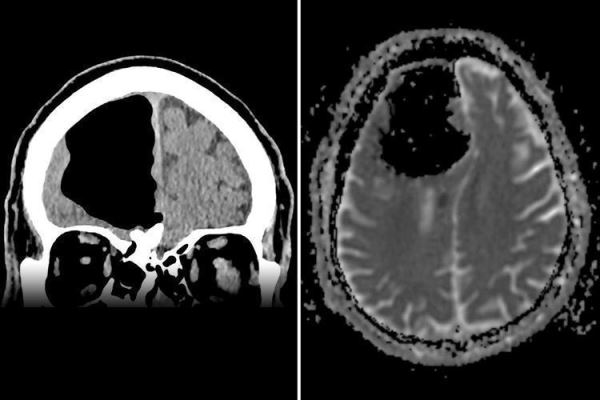

Сначала медики не выявили никаких патологий, придя к выводу о нормальной работе периферической нервной системы. Специалисты предположили инсульт, после чего была проведена компьютерная томография. Результаты очень сильно удивили экспертов: на месте правой лобной доли находилась пустота.

Финлей Браун предположил проведение операции в молодые годы, однако, по словам пациента, ничего подобного в его жизни не было. Осуществленная впоследствии магнитно-резонансная томография показала образовавшуюся в передней части черепа заполненную воздухом полость, которая достигала 9 см в поперечнике. Подобное явление называют «пневматоцеле»: оно может наблюдаться после травм, инфекций или хирургических операций.

В описанном случае причиной стала доброкачественная опухоль — остеома. Она образовалась в области решетчатой кости — непарной кости мозгового отдела человеческого черепа, отделяющей носовую полость от полости черепа. Из-за повреждения кости воздух начал попадать в череп, так что получился эффект одностороннего клапана.